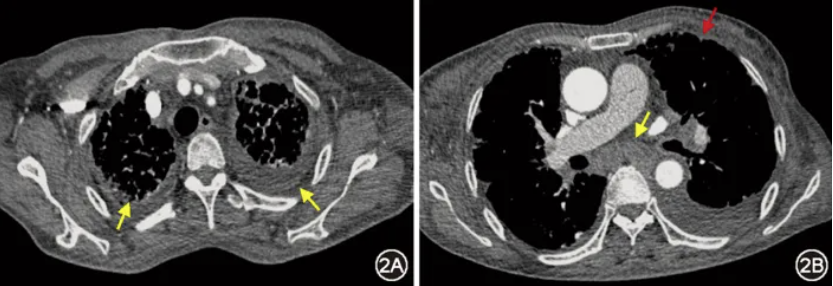

图1 治疗前(2024年9月10日)胸部CT:双肺弥漫网格(图1B红箭头)、磨玻璃影(图1B黄箭头),小叶间隔增厚(图1A箭头),支气管血管束增粗(图1C箭头)

患者女,66岁,因“活动后气短、下肢水肿1年,加重1个月余”于2024年11月25日入院。2023年12月起患者出现活动后气短、下肢水肿,逐渐加重,日常卧床。多次于外院就诊,CT示支气管血管束增粗、小叶间隔增厚、网格及磨玻璃影,伴纵隔淋巴结肿大、胸膜增厚及胸腔积液;纵隔淋巴结活检病理:多量吞噬炭末的异物巨细胞;外院考虑“间质性肺炎伴感染”,间断予抗感染治疗无效。2024年6月14日患者就诊于我院门诊,查血管紧张素转化酶(ACE)77 U/L(参考范围:12~68 U/L),拟诊为结节病,予口服泼尼松40 mg、1次/d,共2周,此后每周减2.5 mg;吗替麦考酚酯0.5 g、2次/d。患者气短仍加重,并新发右乳肿大。2024年9月于我院住院,气管镜下见多发支气管黏膜充血、散在炭末沉积;再次行纵隔淋巴结活检,病理可见少许巨核细胞;支气管肺泡灌洗液(BALF)细胞分类:巨噬细胞百分比99%,中性粒细胞百分比0.5%,淋巴细胞百分比0.5%;BALF T细胞亚群:CD4+/CD8+T细胞比值0.8。完善胸腔积液检查:黄色浑浊,白细胞总数147×106/L,单核细胞百分比93.2%,乳酸脱氢酶150 U/L,腺苷酸脱氨酶10.6 U/L,甘油三酯0.1 mmol/L。胸腔积液及血结核感染T细胞检测(T-SPOT.TB)阳性。胸腔积液、BALF细胞学检查未见瘤细胞。乳腺超声及钼靶:右乳水肿改变;CT表现同前(图1,图2)。结合上述检查,考虑结节病诊断不成立,于2024年9月末停用泼尼松及吗替麦考酚酯。由于病因未明,不除外结核感染,予异烟肼、利福平、乙胺丁醇诊断性抗结核,引流胸腔积液后出院。出院后1个月,患者气短、右乳肿大、胸腔积液仍加重,自行停用抗结核药物,于2024年11月25日再次入院。患者有双侧腕管综合征病史3年,否认疫区及牧区旅居史、家族肿瘤病史。